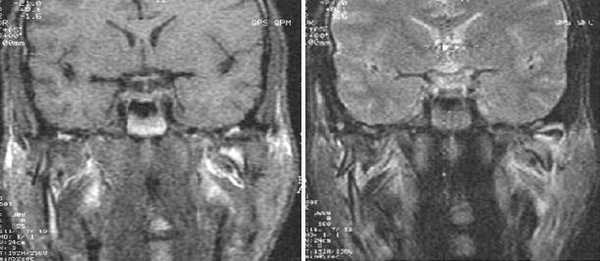

Косо-сагиттальная проекция с закрытым ртом. Нормальный ВНЧС.

Суставной диск не дислоцирован, задняя его часть находится на 12 часах циферблата мыщелка.

Нормальная мобильность диска

Позиция с открытым ртом. Мыщелок сместился вентрально, на уровень суставной ямки. При этом суставной диск сохранил нормальное положение интерпозиции, не давая костным структурам напрямую контактировать друг с другом.